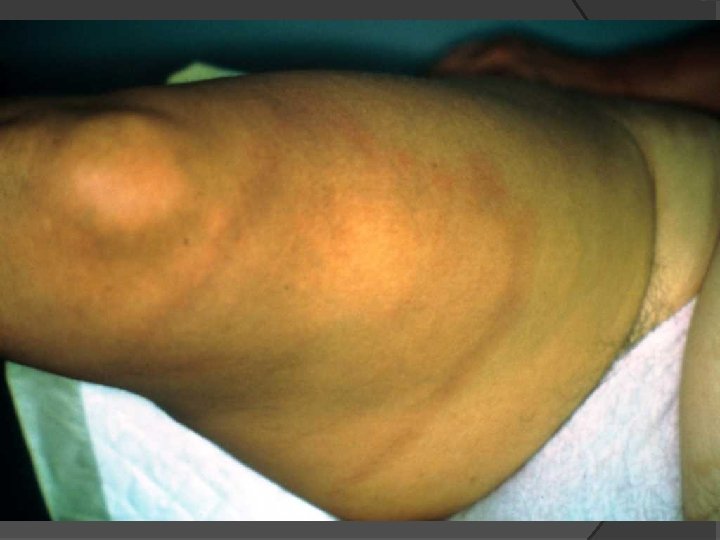

MANIFESTATIONS ARTICULAIRES Arthralgies migratrices et fluctuantes Mono ou oligo-arthrites asymétriques (genou) Ténosynovites Bursites Dactylites Talalgies Ostéo-arthrites Associées à l’ACA dans la phase tardive Luxation des petites articulations, périostites, érosions

ARTHRITES Liquide articulaire Inflammatoire et riche en protéines Synoviale Synovite hypertrophique non spécifique Proche de celle observée dans la PR